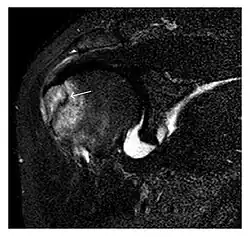

The greater tuberosity of the humerus is also an illustrative location of occult fractures. The osseous injury may follow seizures, glenohumeral dislocation, forced abduction, or direct impaction. They are commonly discovered on MRI in symptomatic patients with suspicion of rotator cuff tear. Coronal images are best suited for detection. They appear as crescentic oblique lines surrounded by a bone marrow edema pattern (Figure 5). The rotator cuff must be inspected since associated ligamentous lesions are common. In the ankle, malleoli and tarsal bones should be checked carefully for any cortical disruptions and radiolucent lines that may reveal a fracture. Awareness of the exact location of the pain will help direct the attention of the interpreter when searching for very subtle signs of fracture (Figure 6).[1]

a

b

Figure 7: Fatigue fracture of the talus in a 25-year-old male basketball player with right hind foot and ankle pain, without history of trauma, and a normal initial radiograph (not shown). (a) One-month followup lateral radiograph shows normal appearance. (b) Sagittal T1-weighted MRI shows an irregular fracture line (arrow) within an ill-defined area of hypointensity corresponding to bone marrow edema.[1]